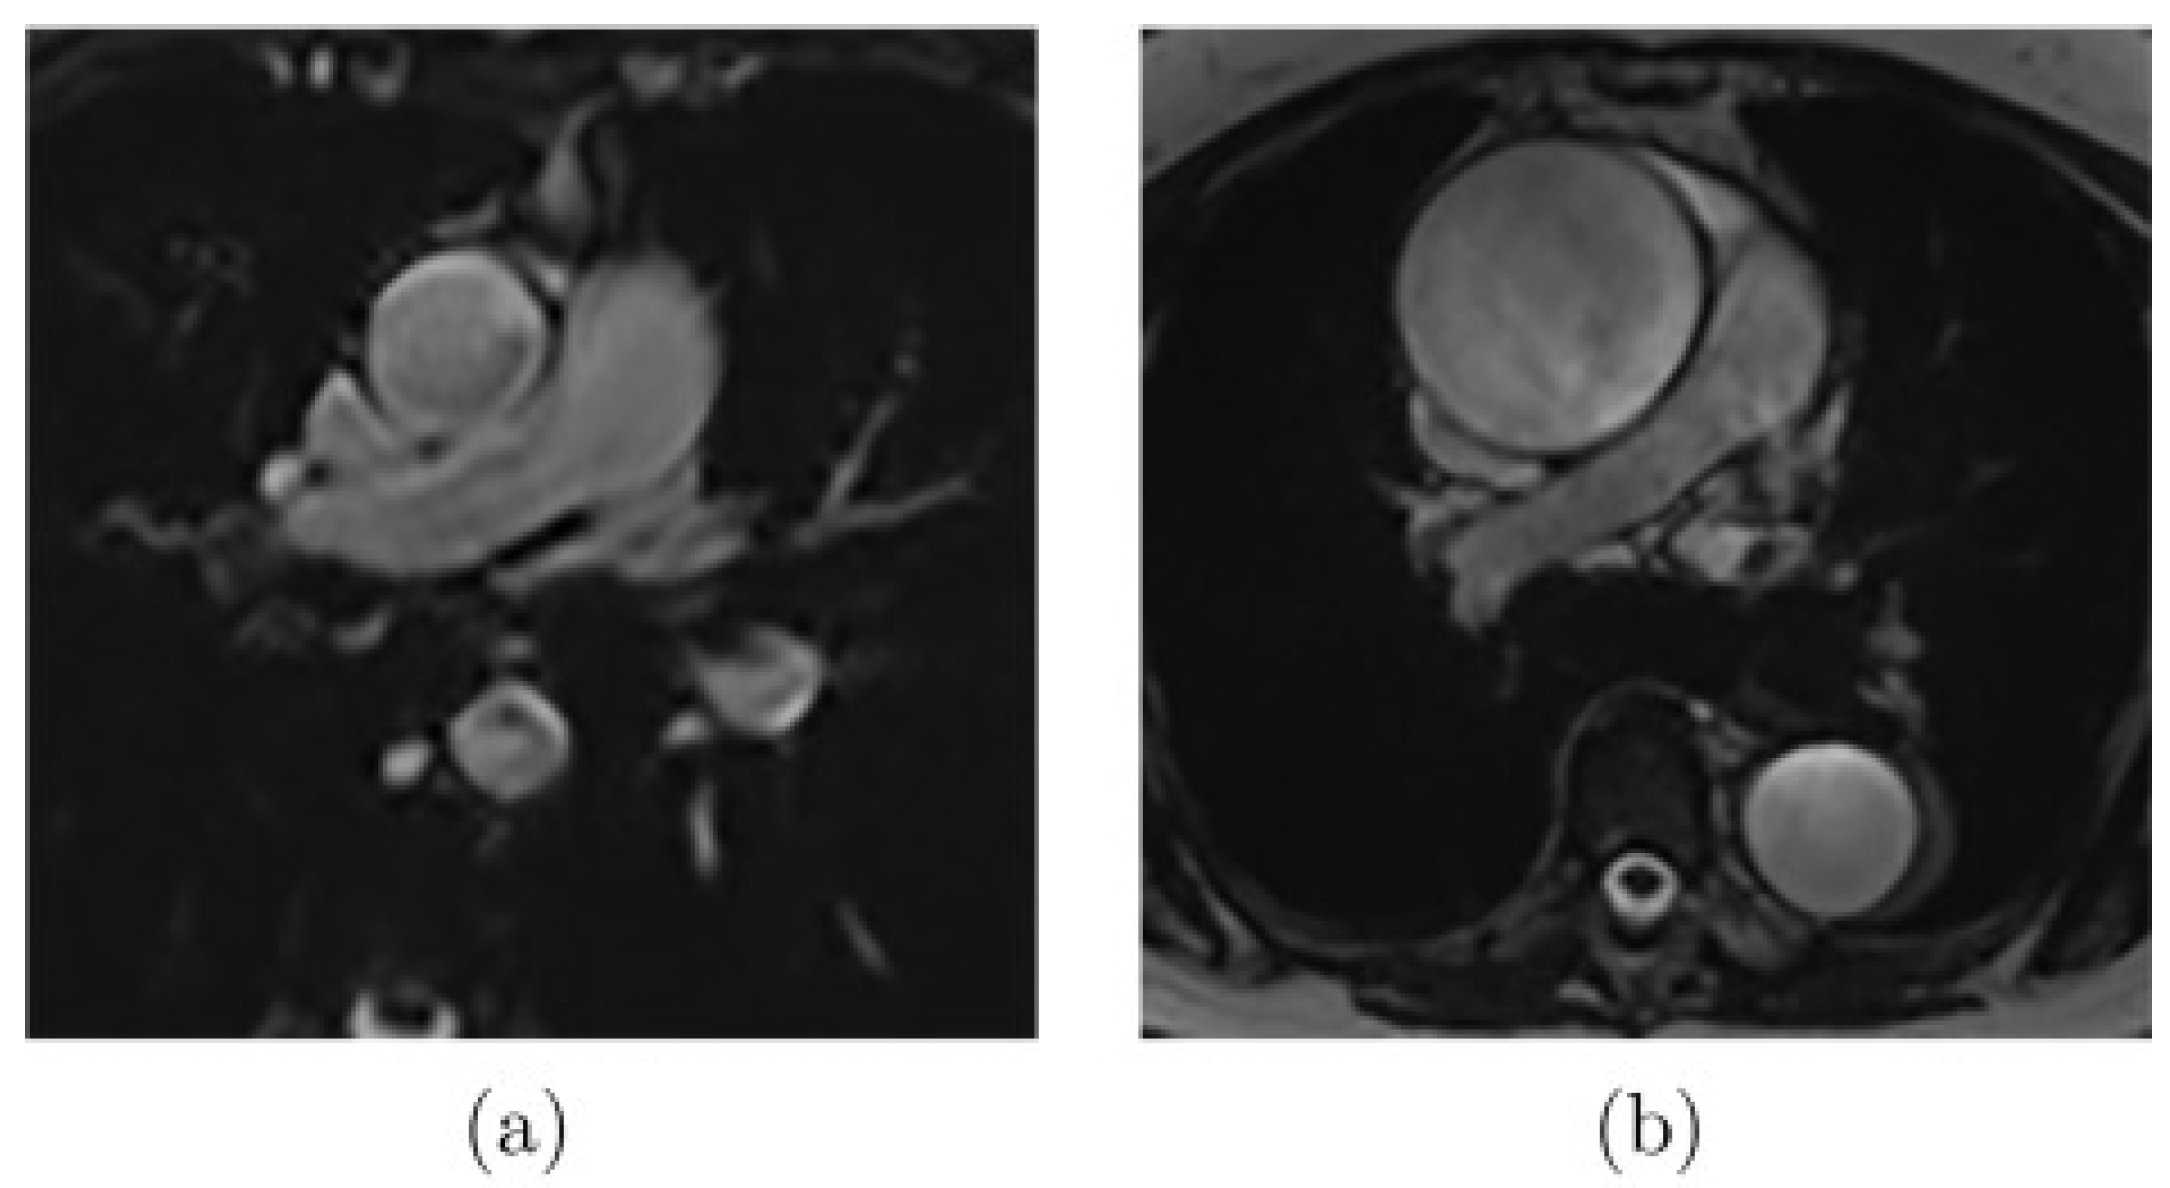

2.3.1. In-Vivo Data: Magnetic Resonance Imaging (MRI)